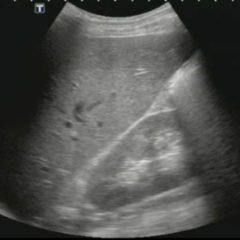

FAST Exam: Normal Suprapubic

FAST Exam - Normal Suprapubic

radiology, trauma, normal, suprapubic, FAST exam, videos, ultrasound, US

UltrasoundVideos